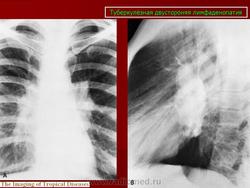

Различают инфильтративный, опухолевидный и малые формы туберкулеза внутригрудных лимфатических узлов. Опухолевидная форма проявляется увеличением размеров лимфатических узлов в результате воспалительной гиперплазии, что обнаруживается при рентгенологическом исследовании. Контуры лимфатических узлов на рентгенограмме и томограммах четкие. Инфильтративный туберкулез внутригрудных лимфатических узлов характеризуется не только увеличением узлов, но и развитием инфильтративных изменений в легочной ткани, в прикорневых ее отделах. Малые формы проявляются незначительным увеличением внутригрудных лимфатических узлов, что выявляется главным образом на томограммах с поперечным размазыванием в прямой или боковой проекциях. Этот вариант заболевания в последнее время встречается чаще, чем в прежние годы.

В современных условиях изменилась структура клинических форм туберкулеза, и появились нетипичные для повседневной практики его проявления. Повышенная восприимчивость к туберкулезу лиц, ранее не инфицированных микобактериями туберкулеза, способствует появлению туберкулеза внутригрудных лимфатических узлов (ТВЛУ) у взрослых. Неосложненное течение ТВЛУ у взрослых проявляется только рентгенологически односторонним или реже двусторонним увеличением различных групп внутригрудных лимфатических узлов. Неправильная оценка изменений во внутригрудных лимфатических узлах при туберкулезе ведет к распространению туберкулезного процесса на бронхи и легочную паренхиму. Возникают различной степени нарушения бронхиальной проходимости, которые сопровождаются развитием воспалительных изменений. Представляю наблюдение осложненного течения ТВЛУ у женщины 61 года, которая была направлена в РОНЦ с диагнозом: центральный рак правого легкого с ателектазом верхней доли. Рис. 1а, б. Верхняя доля правого легкого уменьшена в объеме, однородно уплотнена. Нижний контур доли вогнутый. Органы средостения в верхнем отделе умеренно смещены вправо. Диафрагма на стороне поражения расположена выше обычного. Рис. 2а, б, в, г. Компьютерные томограммы органов грудной клетки. На передней стенке правого главного бронха узелковые образования, перекрывающие частично просвет бронха. Верхнедолевой бронх нитевидно сужен. Верхняя доля правого легкого уменьшена в объеме, верхушечный и задний сегмент ателектазированы.

Неосложненное течение ТВЛУ у взрослых проявляется только рентгенологически односторонним или реже двусторонним увеличением различных групп внутригрудных лимфатических узлов.